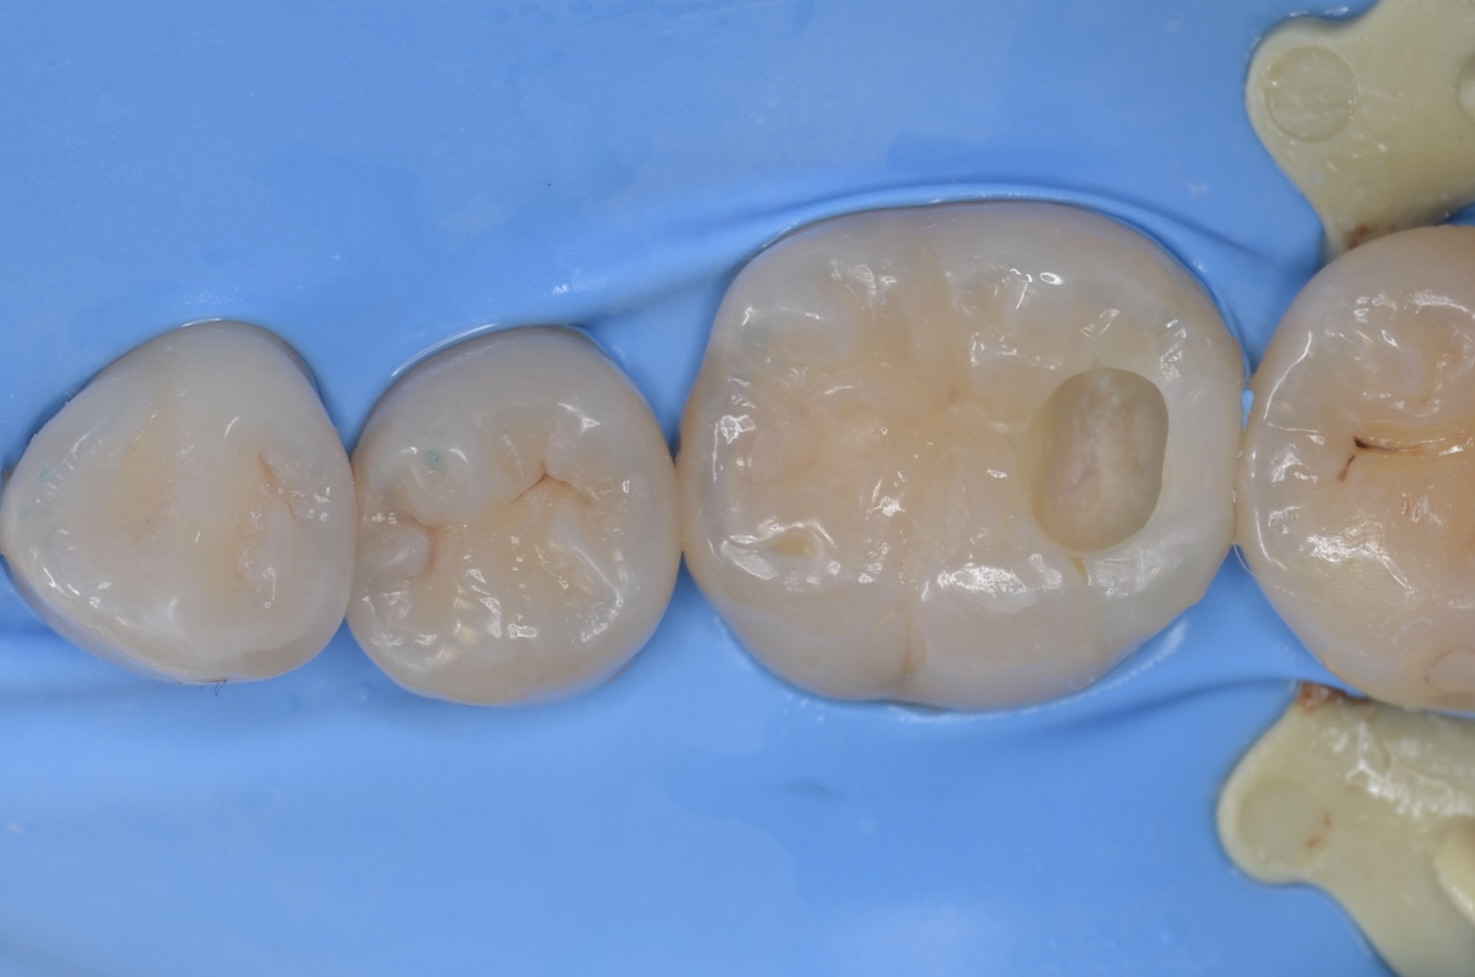

コンタクトをレジン充填

虫歯が中で広がっているので、先に隣接部をレジン充填して仮封しました。次回続きをします。 -

露髄

1週間後に治療の続きをします。 完全に虫歯を取り切ると露髄しました。 -

MTAセメント

露髄面にMTAセメントを充填しました。 -

スーパーボンド

スーパーボンドでMTAセメントを覆います。 -

ダイレクトボンディング

天然歯の自然な形態を模倣してレジンを充填しました。 -